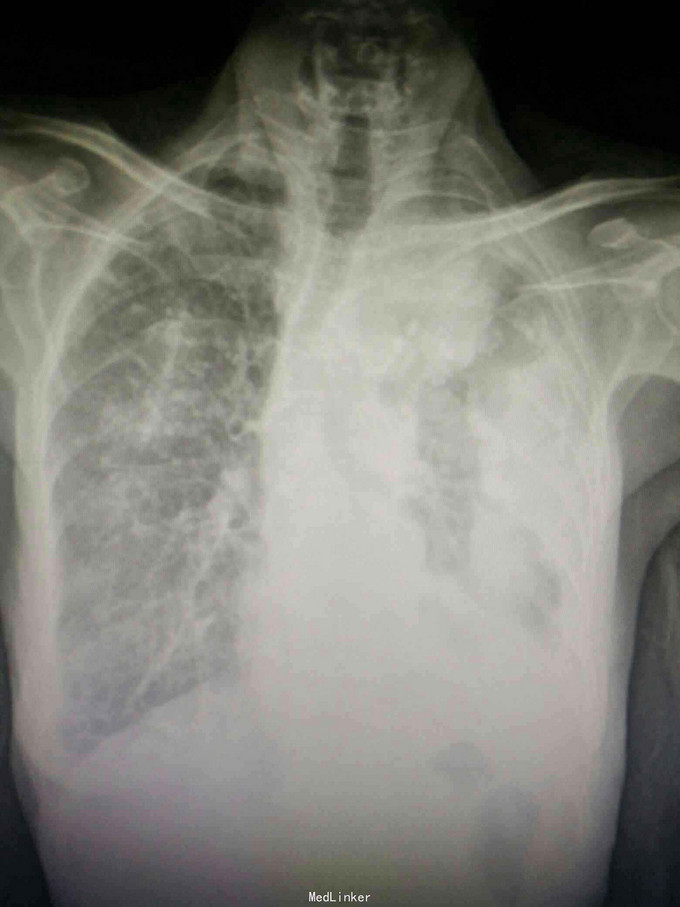

患者陈某某,女,69岁。 主诉:反复咳嗽咳痰1年余,加重伴气促1月。 病史:1年前出现咳嗽咳痰,阵发性,少量白痰,无发热,无盗汗消瘦,无胸闷胸痛,未予重视。1月余前出现咳嗽咳痰加重,伴气促,活动后明显,无夜间阵发性呼吸困难,当地医院胸片示左侧胸膜多发肿块,两侧胸膜增厚钙化,随后至我院就诊。 既往史: 有石棉接触史20余年,40年前行输卵管结扎术,26年前行阑尾切除术,否认其他疾病史,否认烟酒史。

查体:神志清,精神可,生命体征平稳。两肺呼吸音粗,未闻及干湿性啰音。 辅查: 血气分析:PH7.43, 二氧化碳分压43mmHg, 氧分压77mmHg, 氧饱和度95%。 血常规:WBC7.5x10∧9/L, NE77.8%, Hb132g/L, plt231x10∧9/L。 尿常规,粪便常规,凝血功能,肿瘤标志物,CRP, 免疫功能,肝肾功能电解质无明显异常。 痰培养,痰找抗酸杆菌阴性。 心电图无明显异常。 心脏彩超:主动脉瓣局部退行性变,左室舒张功能减退,轻度肺高压。 腹部B超无异常。 胸部增强CT:双侧多发胸膜斑,左侧胸膜弥漫结节状及团块形成,考虑石棉肺伴左侧胸膜继发性恶性间皮瘤可能。

入院诊断:左侧胸膜肿物:胸膜间皮瘤? 诊治经过:予对症支持治疗,行CT引导下胸膜活检 病理:结合免疫组化和临床病史,符合恶性间皮瘤。 治疗:患者明确诊断后予化疗前预处理,择期行培美曲塞+铂类化疗